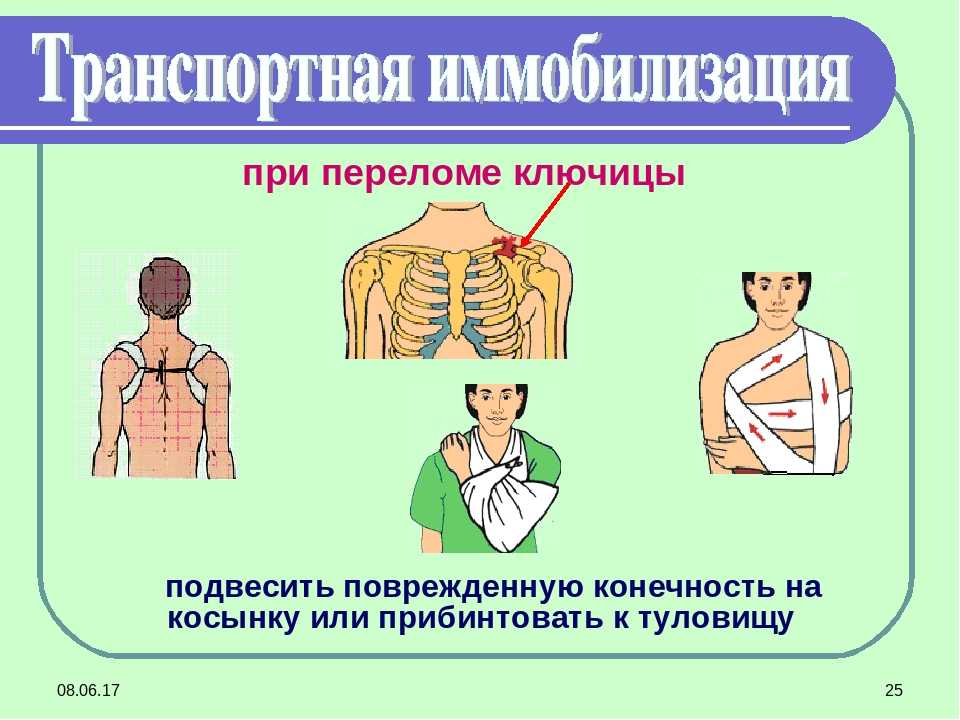

Вывихи и переломы ключицы презентация - 85 фото